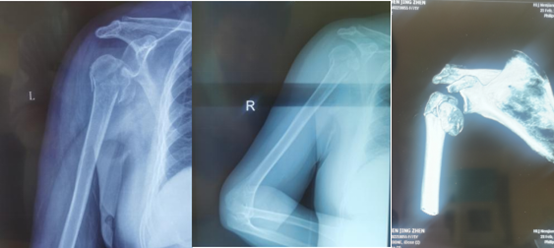

71 岁的陈女士,因不慎跌倒致右肩关节受伤,当地医院鉴于骨折复杂手术难度大,建议转院。陈女士及其家属驱车 1000 公里从东北来到天津,慕名求助于泰达医院。经骨二科董荣华主任门诊收入院,诊断为右肱骨近端粉碎性骨折。

住院后,骨二科主管医师迅速完善术前检查与评估。王建华主任组织术前讨论,考虑到患者高龄、骨质疏松且骨折情况复杂,复位固定困难,内固定手术可能无法实施,决定准备半肩置换假体。尽管半肩置换手术在泰达医院尚属首次,但在医院领导的大力支持下,设备科紧急联系厂家,快速完成临时采购任务。经过与患者家属充分沟通,决定于入院后第四天手术,依术中情况选择内固定或半肩置换方案。

术前影像资料

术中攻坚:精准施治,技艺精湛

2 月 28 日,手术当日,在麻醉科与手术室的全力配合下,王建华主任带领团队为患者实施手术。术中发现骨折情况比预期更为严重,肱骨头碎裂,多块关节面游离且脱位,骨质疏松骨缺损明显,复位内固定已不可能,果断决定行半肩置换术。凭借丰富的经验与精细操作,王主任精准恢复肱骨头高度与后旋角度,原位固定修复了大小结节,恢复了肩袖的完整性及功能,重建了患者的肩关节动力系统。